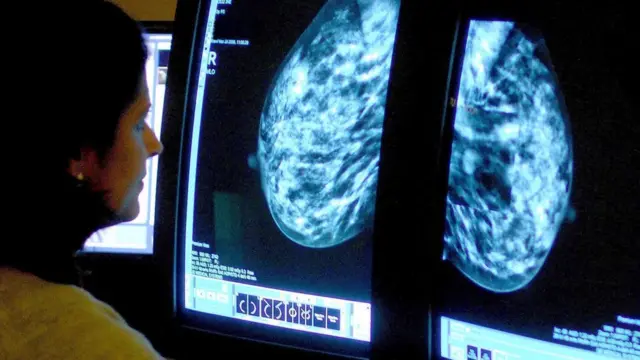

Fuente de la imagen, PA